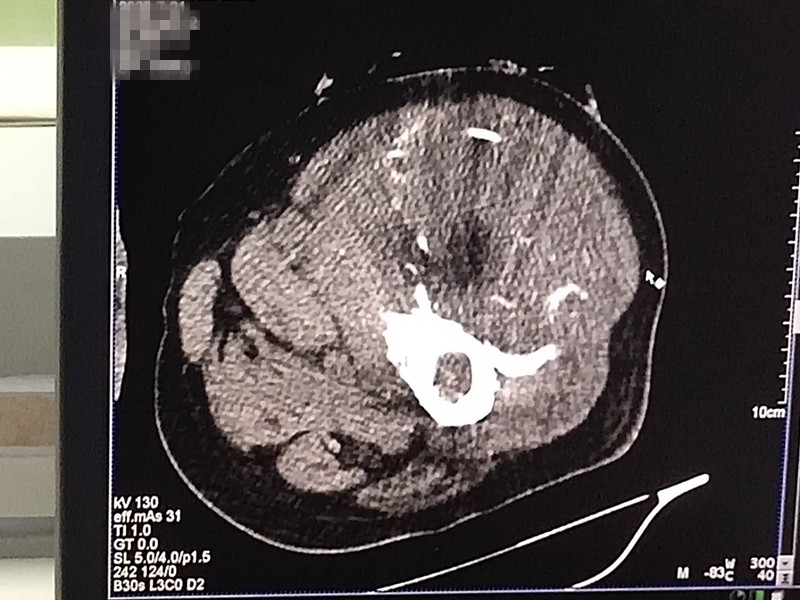

75岁腿部软组织肉瘤氩氦刀冷冻消融